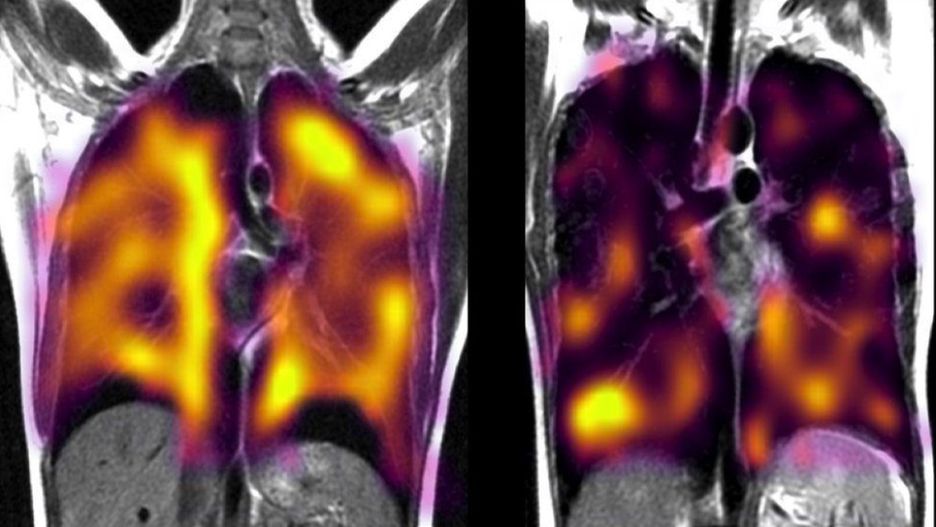

Po lewej stronie widać płuca osoby zdrowej. Po prawej – tej, która ma za sobą długi COVID Po lewej stronie widać płuca osoby zdrowej. Po prawej – tej, która ma za sobą długi COVID

Zespół naukowców z Uniwersytetu Oksfordzkiego zwrócił się do 11 pacjentów. Do ich przebadania wykorzystano nowatorską metodę obrazowania płuc z wykorzystaniem ksenonu. Pozwala ona na lepsze uwydatnienie poszczególnych obszarów organu.

Jak podaje BBC, w wyniku badań z wykorzystaniem ksenonu doszło do niepokojących ustaleń. Naukowcy odkryli, że osoby chorujące na długi COVID, które doświadczały na początku zakażenia ostrych duszności, nawet po pozornym wyzdrowieniu mają ukryte uszkodzenia płuc.